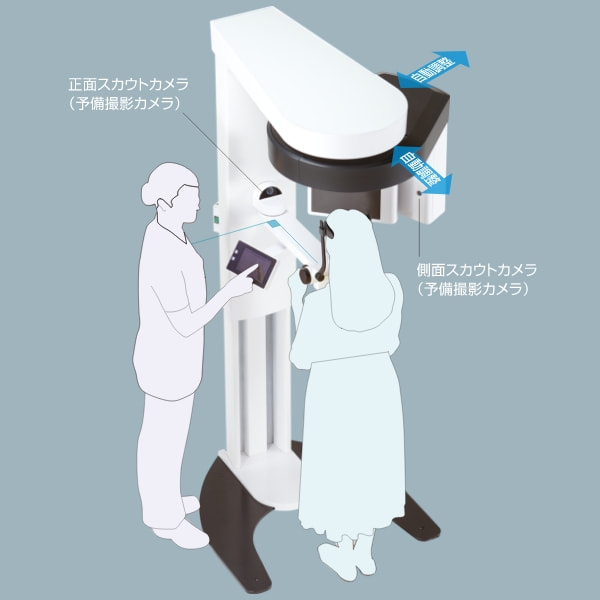

タッチパネル画面の映像を見ながら、容易に位置付けできる2方向カメラスカウト

タッチパネルでの画面操作と連動して、撮影装置が位置を合わせるので、患者さんは動く必要がありません。

またカメラスカウトに加え、2方向のレントゲンスカウト撮影で、撮影位置を設定することもできます。

位置付け時、患者さんの正面と側面に備え付けられたカメラで、2方向からの顔貌撮影を行います。

その画像はタッチパネル画面に表示され、ダイレクトな操作で撮影位置や撮影範囲の設定を行うことができます。

さらに、位置決め時のスカウト撮影画像は撮影画像と共に記録されます。

CTやパノラマ撮影に関わるスタッフの初期教育への活用や、撮影時位置付けの再現性向上にも役立てることができます。